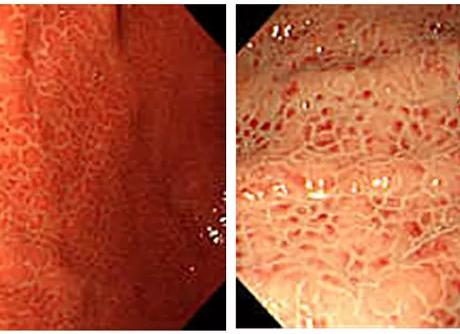

Эритематозная гастродуоденопатия — переполнение кровеносными сосудами внутренней поверхности стенок желудка. Патология обычно затрагивает лишь внешний слой, не доходя до глубоких уровней. Выявляется она при помощи фиброгастродуоденоскопии (ФГДС). Это исследование проводят при помощи специального прибора в форме шланга, оснащённого камерой и осветительным аппаратом. Процедура проводится только натощак.

Другими словами, эритематозная гастропатия это такое явление, которое характеризует покраснения и отеки на слизистой желудка. Слабовыраженные воспаления особой опасности организму не несут, хотя его могут диагностировать как поверхностный гастрит. Если патология выявлена отдельным явлением без посторонних заболеваний, то метод лечения значительно упрощается. Покраснением слизистой желудка нельзя пренебрегать. Избавиться от неё можно лишь соблюдая правильный, предписанный врачом режим питания.

Важным диагностическим методом является гастроскопия. Однако этот метод при данной патологии показан не всем. Если есть подозрение на то, что болезнь вызвана механическим повреждением или химическим воздействием, то проведение процедуры может еще больше усугубить течение. Поэтому проводят гастроскопию только в стадии ремиссии.

При проведении могут отмечаться такие признаки, как:

• покраснение и отёчность слизистой;

• инфильтрация защитными клетками организма – лейкоцитами;

• полнокровные сосуды.

Под гастропатией эритематозной подразумевают покраснение слизистой желудка, которое может сопровождаться ее отеком, кровоточивостью и повышенным образованием слизи.

Как мы уже говорили, данный признак определяется при исследовании желудка с помощью эндоскопа – фиброэзофагогастродуоденоскопии (ФЭГДС).

Покраснение слизистого слоя желудка провоцируется рядом неблагоприятных факторов, например, грубой, острой и слишком горячей пищи. Под воздействием причинного фактора в пораженной зоне желудка активизируется микроциркуляция, что и придает ей красный цвет.

Отличительная черта данного эндоскопического признака заключается в том, что затрагивается исключительно слизистой слой желудка, а более глубокие слои органа остаются интактными.